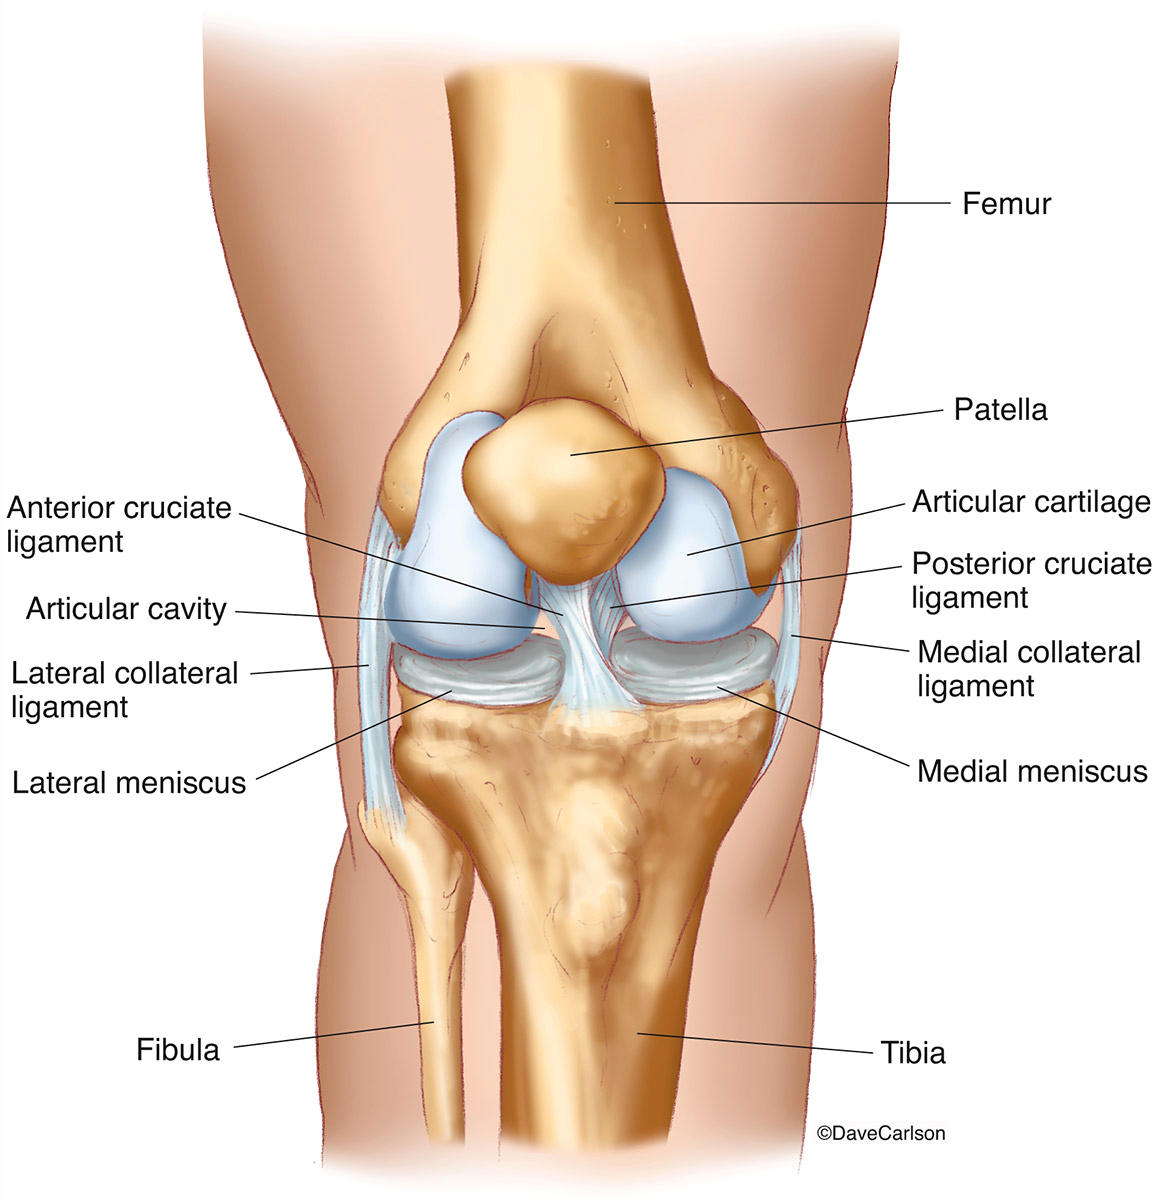

Анатомические изображения менисков и коленного сустава